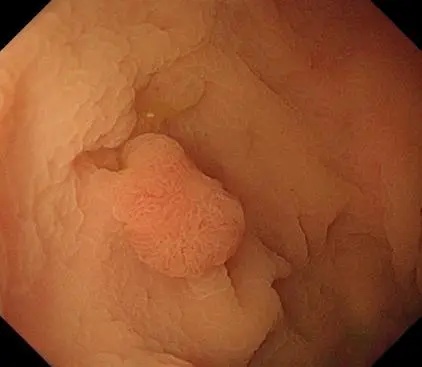

原来,是我院功能科主任、消化内科副主任刘哲为患者进行胃肠镜检查时,发现患者直肠处有一个大小1.5cm*1.0cm的息肉。凭借敏锐的观察力和扎实的专业素养,刘哲主任判断,这很可能是早癌。

白光内镜下观察情况